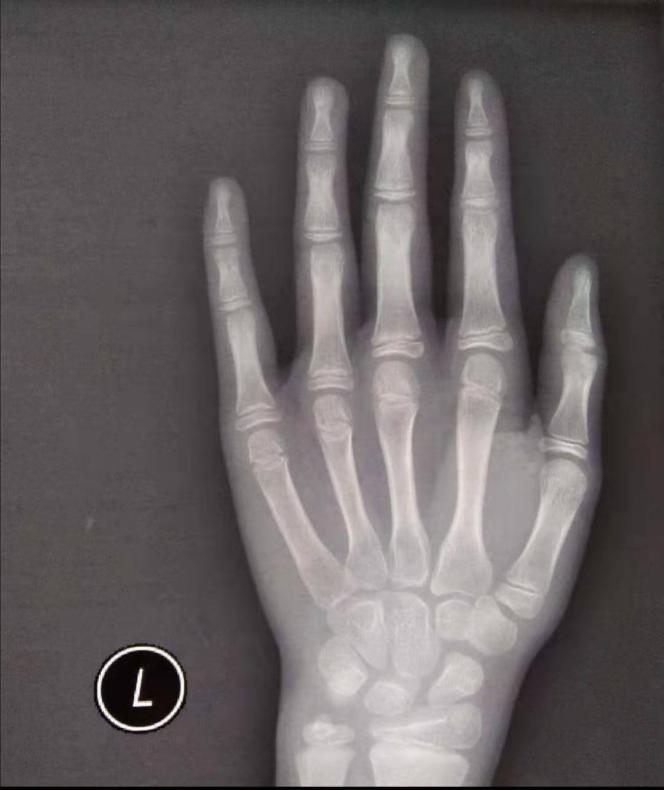

这个孩子因为身高不够,疑似出现月经和乳腺肿块到医院诊治,入院以后查骨龄提示:约为11周岁女童,很显然超过了实际年龄。而且乳腺彩超示:乳房增生。生长激素也偏高。考虑诊断性早熟。基本治疗方案为: